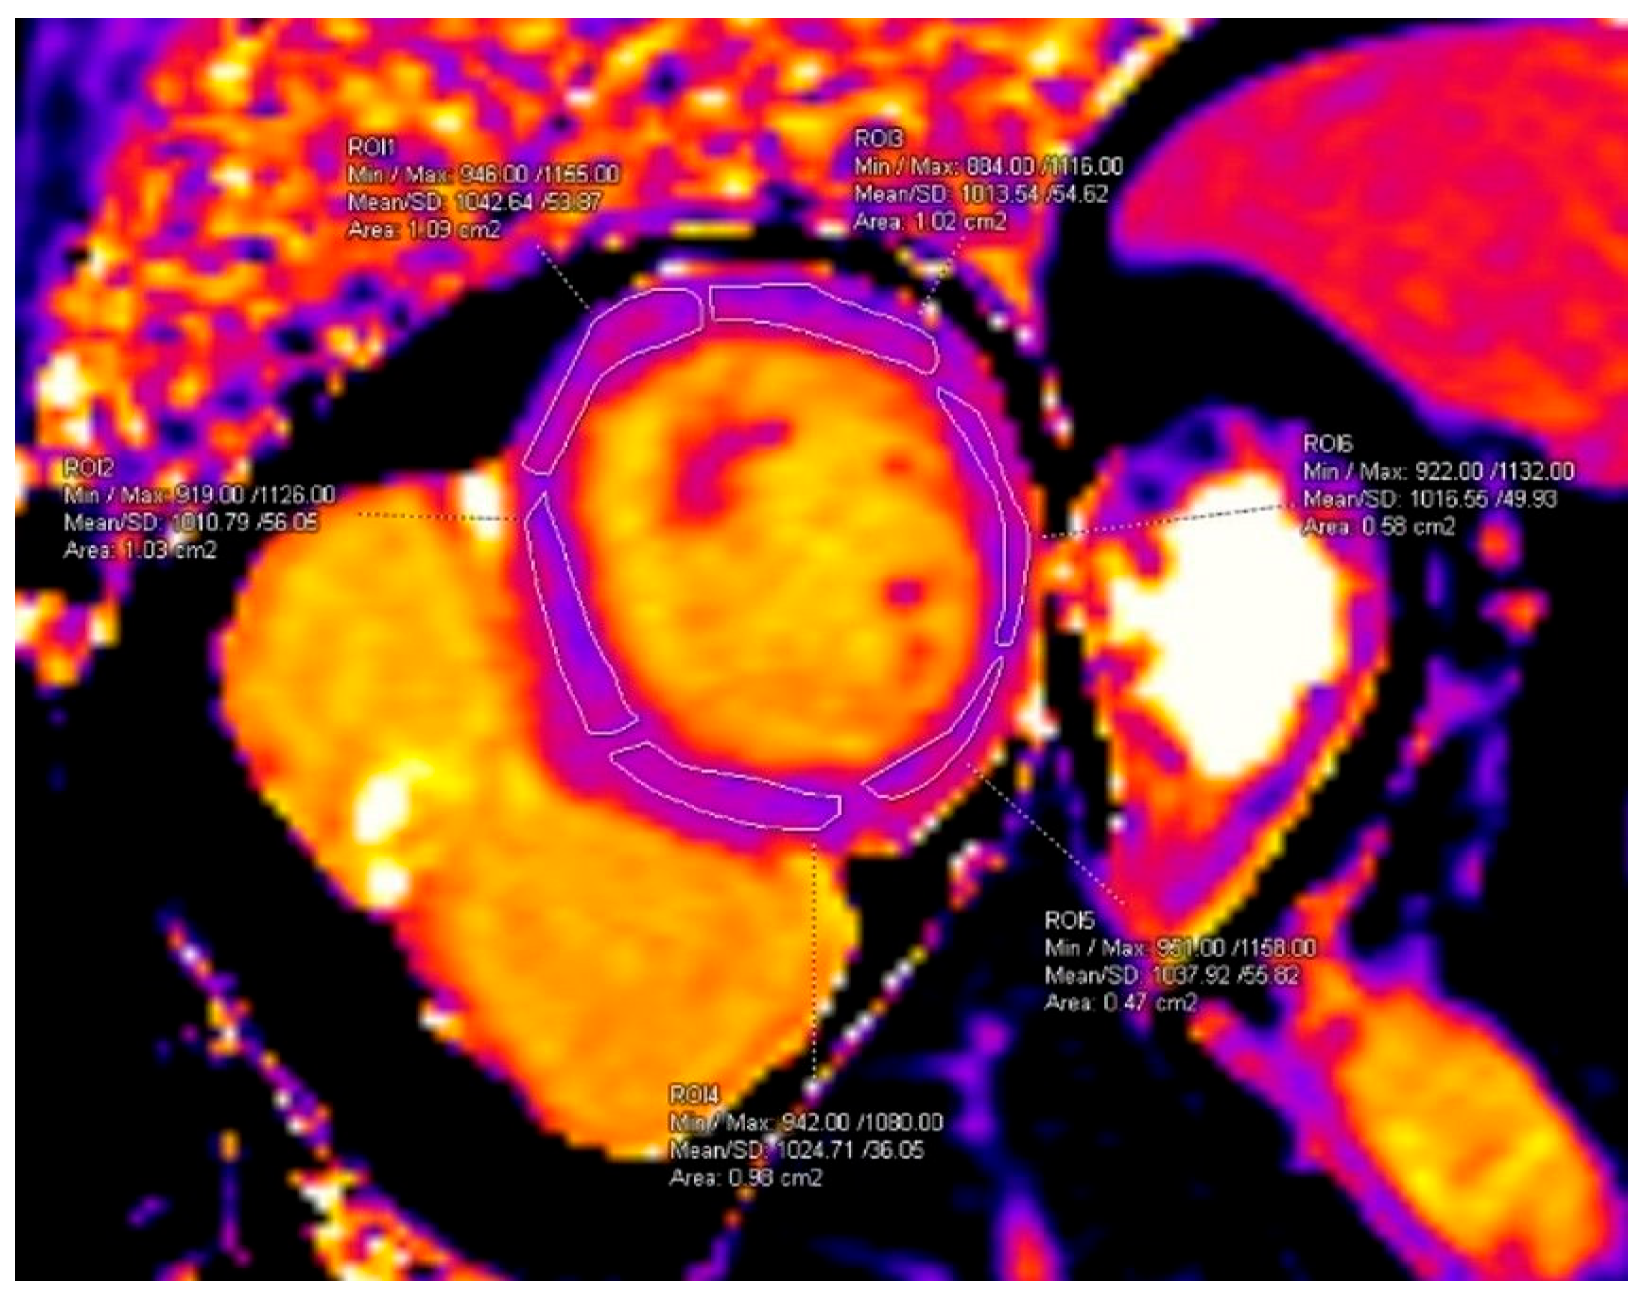

T1 and T2 mapping measurements were performed on the basal short-axis slice, segmented into six standard myocardial segments as previously described [10], ensuring exclusion of the blood pool (Figure 1).

Figure 1. Segmental measurement of T1 values. ROI area values are displayed automatically by the software as “cm2” and correspond to cm2.